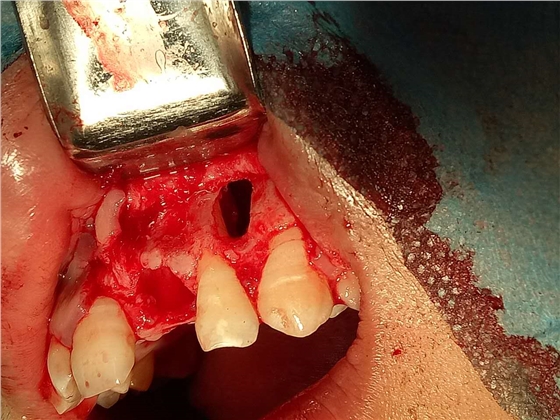

死髓牙2度,沒(méi)保留價(jià)值了,外傷造成的外吸收,即使到充也容易出問(wèn)題。和患者溝通,要求做種植,用了兩個(gè)骨膠原,側(cè)切、尖牙沒(méi)事,側(cè)切做了一次根充